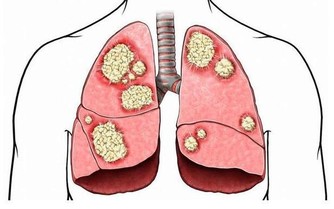

同時,洋蔥也是一種十分有營養的植物,不僅含有豐富的維生素、鈣、鐵、磷等礦物元素以外,還好有很多對人體有益的化合物。並且網上也流傳著一種說法,那就是洋蔥對糖尿病和癌症都很有療效。因此,很多人都喜歡食用洋蔥。